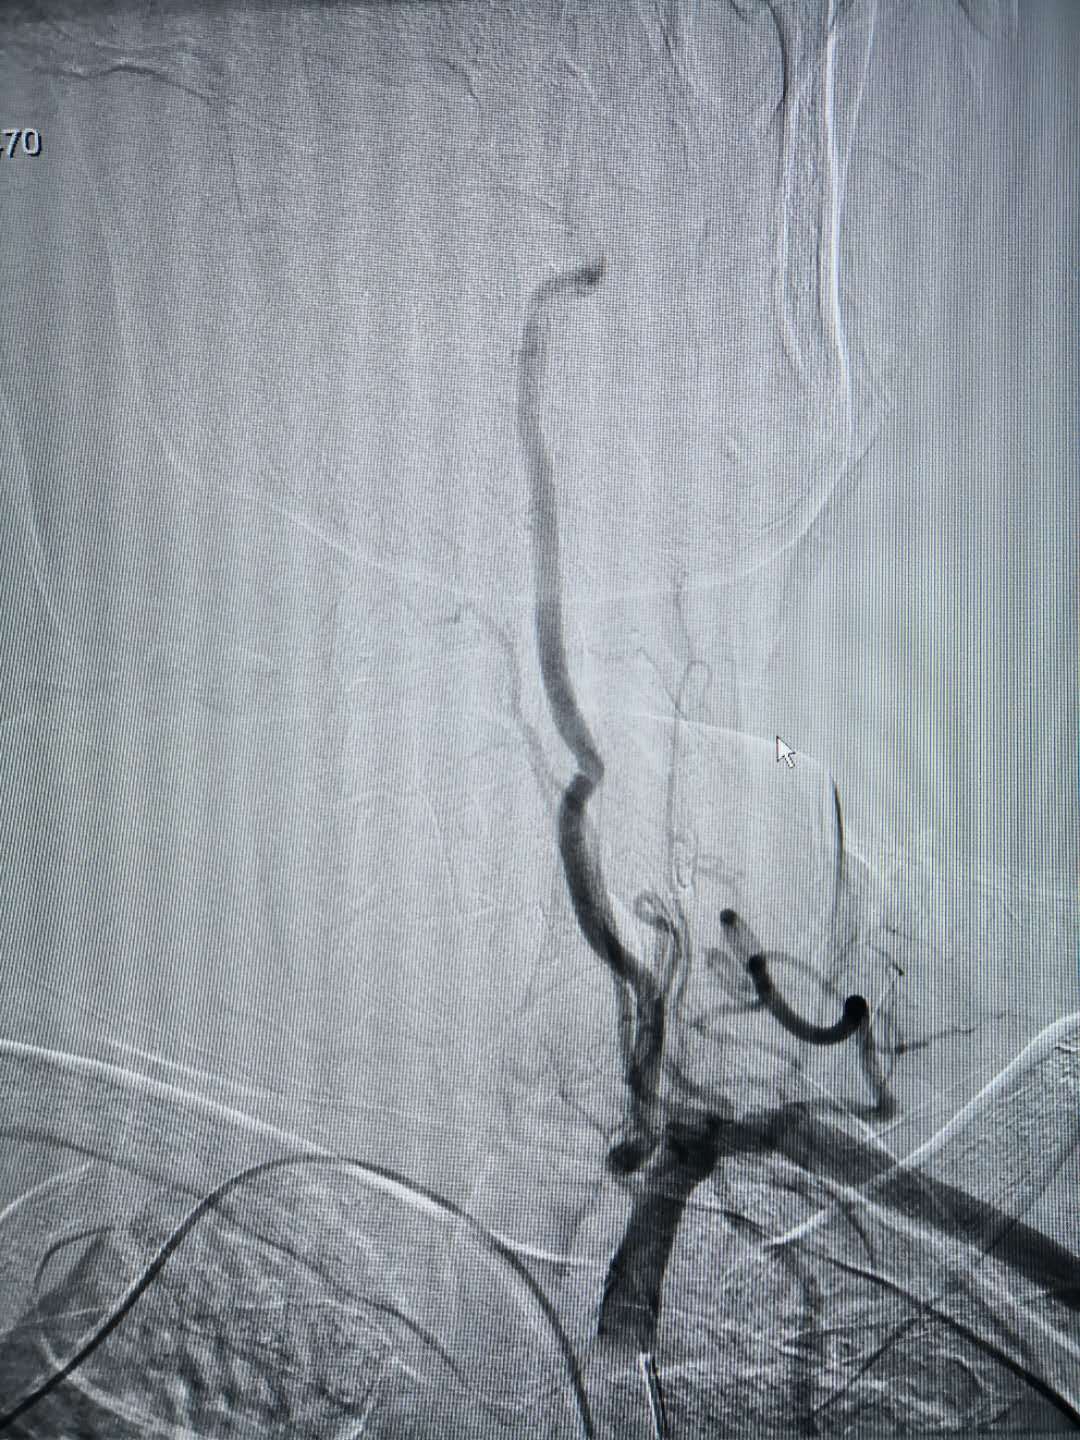

置入造影導管后相關血管造影圖,所選擇的血管清晰可見

經動脈鞘管置入造影導管行造影術 經橈動脈穿刺置入動脈鞘管 術后:使用小巧的橈動脈壓迫器壓迫固定橈動脈